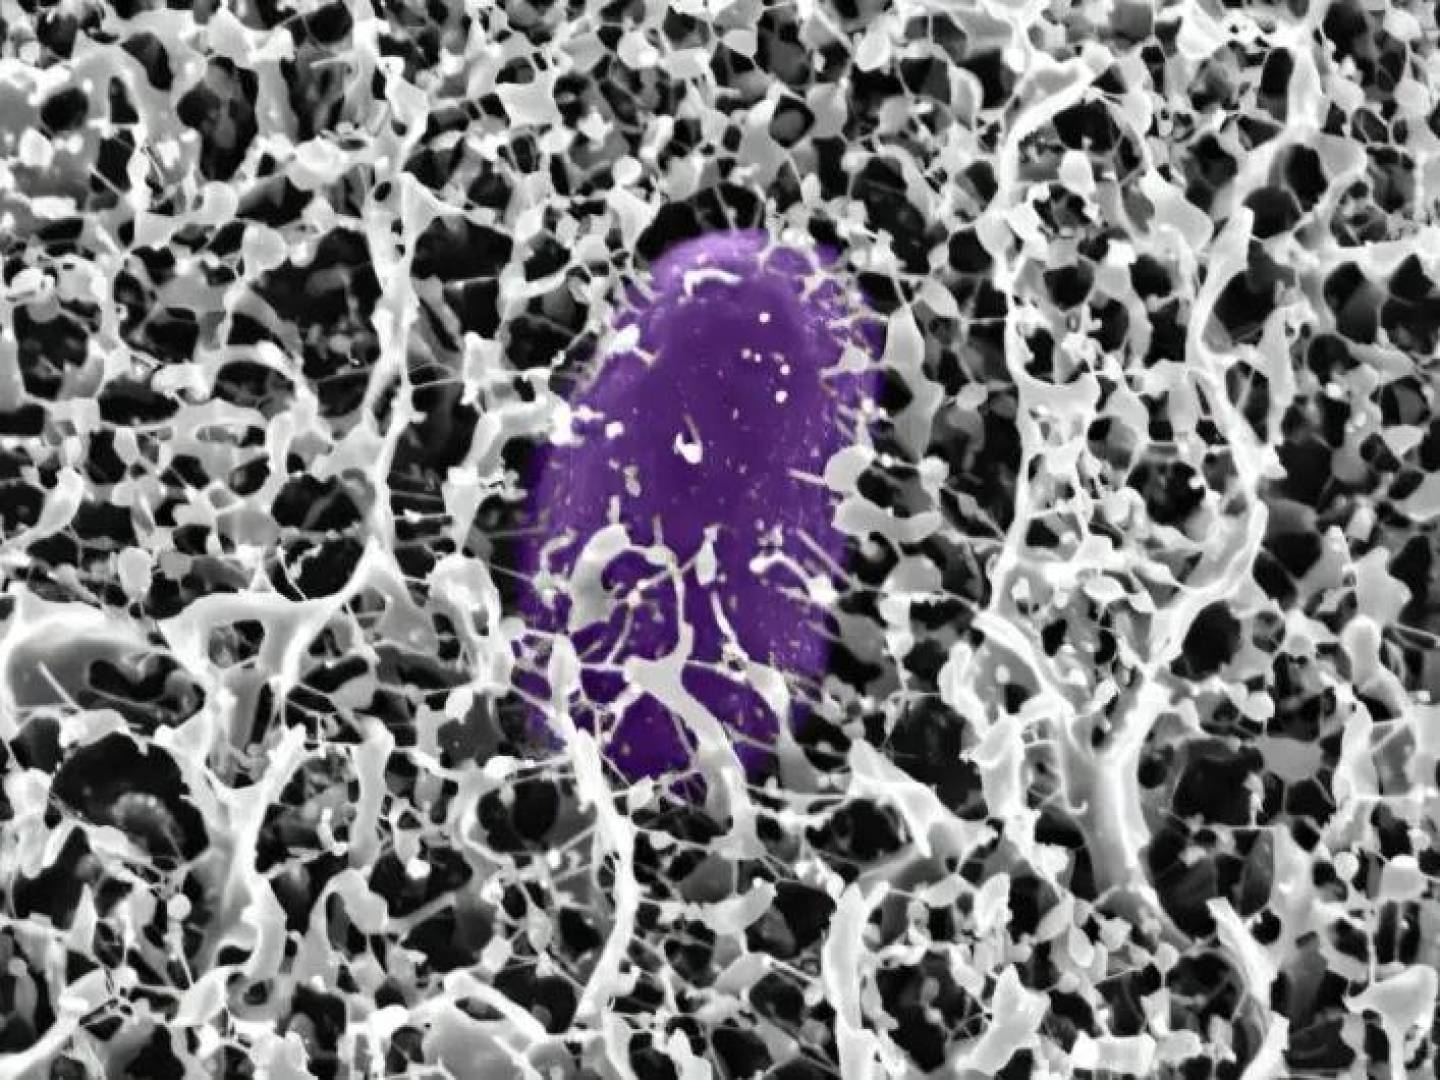

Anti-PC وتصلب الشرايين

يقول البروفيسور يوهان فروستيجارد: "يمكننا أن نظهر أن انخفاض مستوى الأجسام المضادة الطبيعية للفوسفوريل كولين يمكن استخدامه كمؤشر خطر لأمراض القلب والأوعية الدموية لدى النساء، بغض النظر عن عوامل الخطر المعروفة سابقا". وقد أظهرت الدراسات السابقة أن هذه الأجسام المضادة لها تأثير مضاد للالتهاب، مما يعني أنها تحمي من تصلب الشرايين.